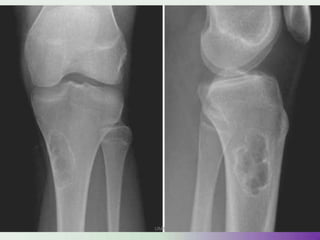

Site

• 55% AROUND THE KNEE

• 10% in the distal radius

• 6% in the proximal humerus

• SPINE rarely involved (commoner in the sacrum)

• In the head and neck region the maxilla and mandible are more commonly involved.

RADIOLOGY

Type of Osteolysis

• Geographic destruction (I)

• Moth-eaten (II) Permeative(III)

Lodwick

1A 1B 1C

UMY

• Expansile

• TRABACULATION

PURE LYTIC (60%) FINE TRABACULTION(40%)

‘E’ OF GCT

• EPIPHYSEAL

• ECCENTRIC

• EXTENDED CURETTAGE

• EXCISION –IF EXTENDED CURETTAGE FAILS